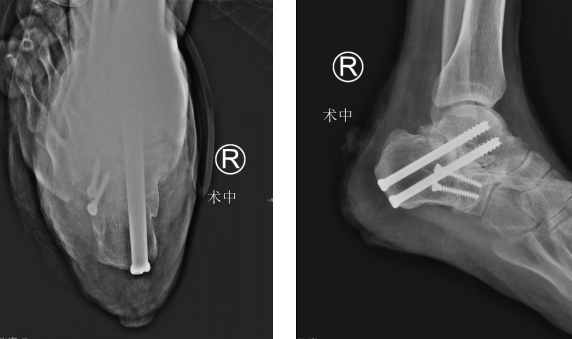

当天,小王办理了住院手续,然后做了术前的相关检查,明确了诊断之后,曹广超主任赵亮医生团队为小王制定了第二天的手术方案,第二天下午曹主任、赵亮医生团队就在腰麻下为小王做了右跟骨截骨矫形、距下关节融合术,术中沿着跟骨原有的骨折线将跟骨凿开,重新整复,考虑距下关节退变严重,已经没有保留的条件,于是就给予距下关节融合,跟骨截骨矫形内固定治疗,手术后小王平安返回了足踝病房。

术后在赵亮医生的指导下,小王进行康复功能锻炼。赵医生说,定期复查,小王三个月后就可以正常行走。